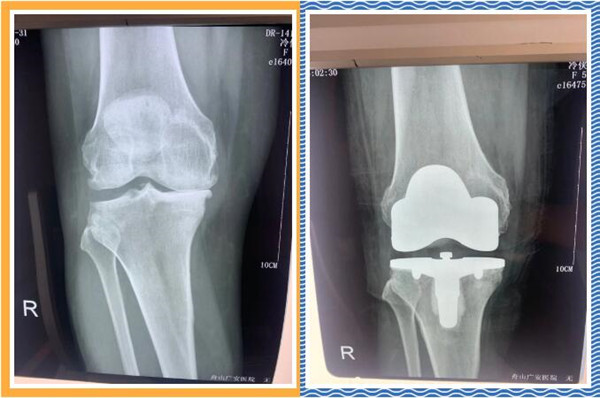

經(jīng)查體及拍片檢查后,危立軍副院長認(rèn)為冷大姐是右膝關(guān)節(jié)嚴(yán)重磨損,是年輕時干重體力工作導(dǎo)致關(guān)節(jié)提前磨損,年紀(jì)是輕了一點,但關(guān)節(jié)置換是一種相對較好的辦法,可早期恢復(fù)關(guān)節(jié)正常,改善生活質(zhì)量,建議其入院并接受人工膝關(guān)節(jié)表面置換手術(shù)。。

三天后,冷大姐接受了右膝關(guān)節(jié)置換手術(shù)。手術(shù)由危立軍副院長主刀,在關(guān)節(jié)鏡下順利完成。術(shù)后,冷大姐恢復(fù)良好。同時,在經(jīng)過院部協(xié)商后,減免了冷大姐的部分手術(shù)費用和住院治療費用。出院那天,冷大姐熱淚盈眶,感謝的話說了又說。